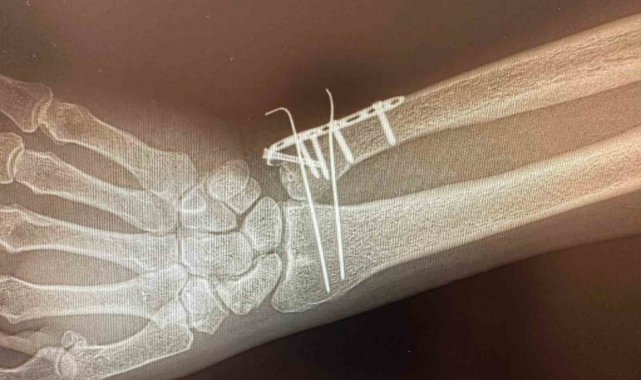

C Kollu Skopinin ameliyathane ortamında hastanın iç yapısını anlık ve hareketli olarak görüntüleyen, X-ray tabanlı taşınabilir bir röntgen cihazı olduğu bildirildi. C şeklindeki yapısı sayesinde her açıdan görüntü alabilen cihazın özellikle ortopedi, travmatoloji, beyin cerrahisi, üroloji ve kardiyoloji işlemlerinde yüksek çözünürlüklü görüntü sağlayarak müdahalelerin daha güvenli ve hızlı yapılmasına imkan tanıdığını aktarıldı.

Cihazın özellikle kırıkların düzeltilmesi, vida ve plak uygulamaları, kalça ve diz protez ameliyatları gibi ortopedi ve travmatoloji işlemlerinde etkin şekilde kullanılacağı ifade edildi.